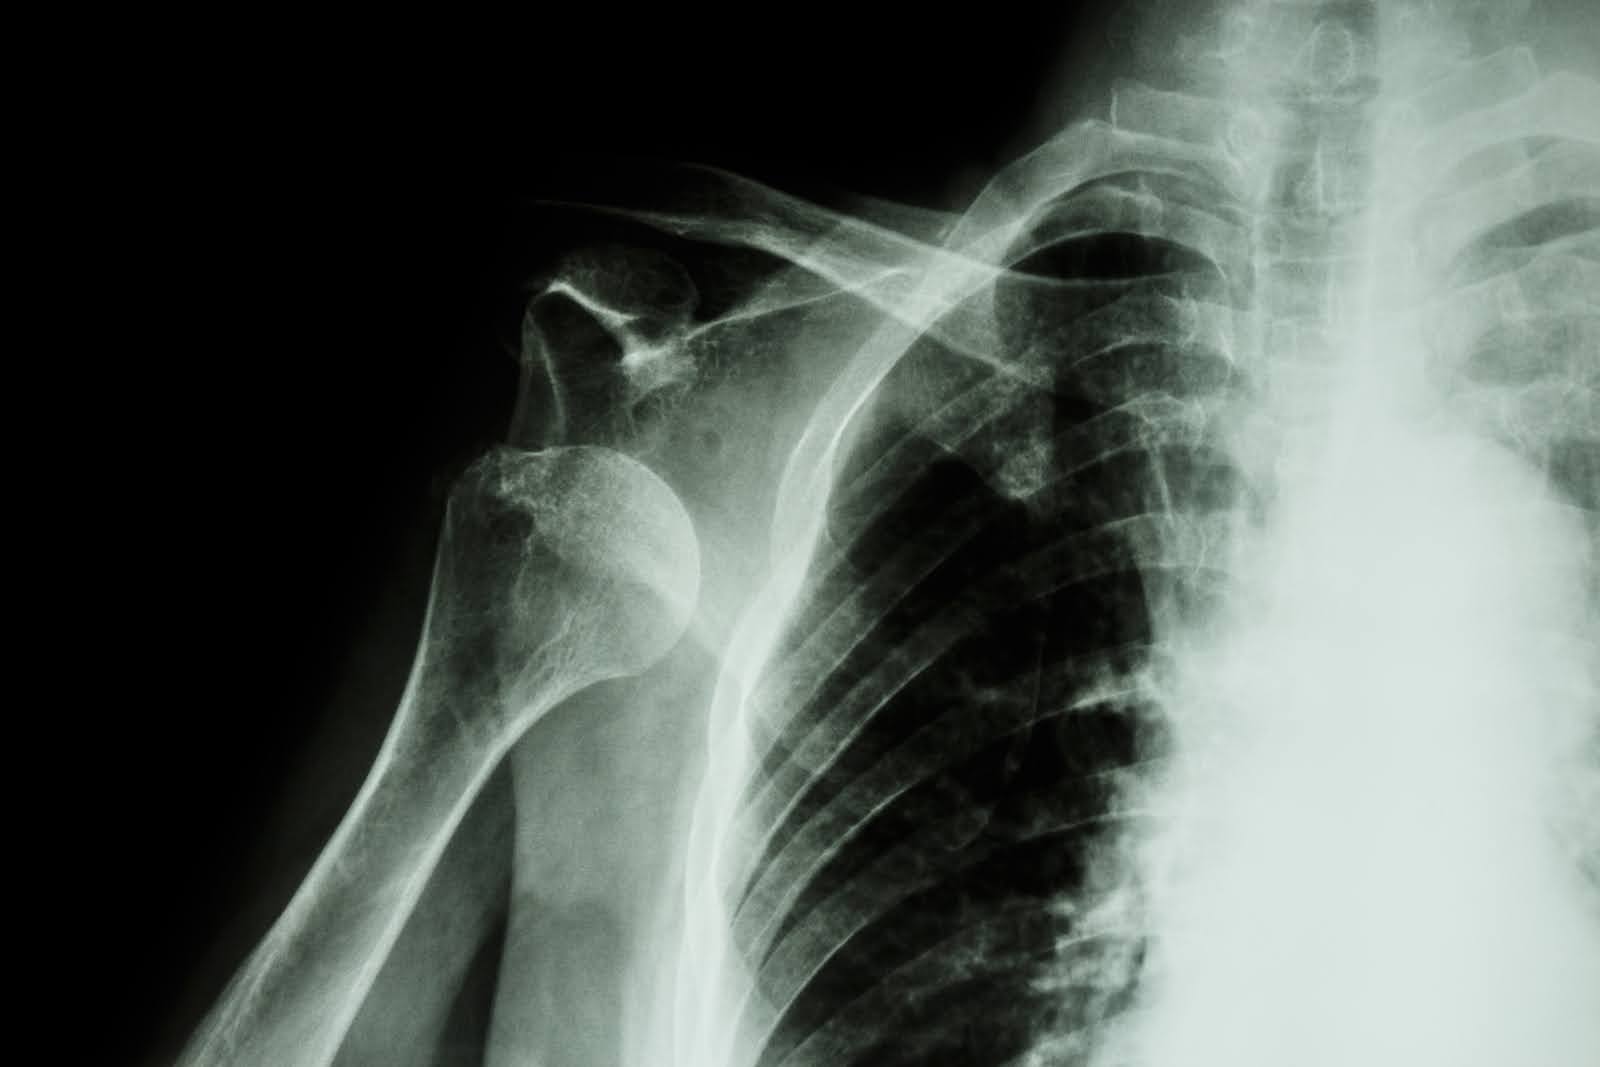

A shoulder dislocation occurs when the upper arm bone (humerus) becomes separated from the shoulder socket (glenoid). Unlike other joints that rely heavily on bone structure for stability, the shoulder depends primarily on muscles, tendons, and ligaments to maintain proper positioning. This design allows for an exceptional range of motion but creates inherent instability that predisposes the joint to displacement.

The shoulder can dislocate in several directions, with anterior (forward) dislocations being by far the most common, accounting for approximately 95% of all cases. Posterior (backward), inferior (downward), and superior (upward) dislocations can also occur but are much less frequent and often associated with more severe complications.

Healthcare providers begin with a thorough physical examination to assess the extent of injury and check for associated complications. X-rays are typically obtained to confirm the dislocation direction and identify any fractures that might have occurred during the injury.